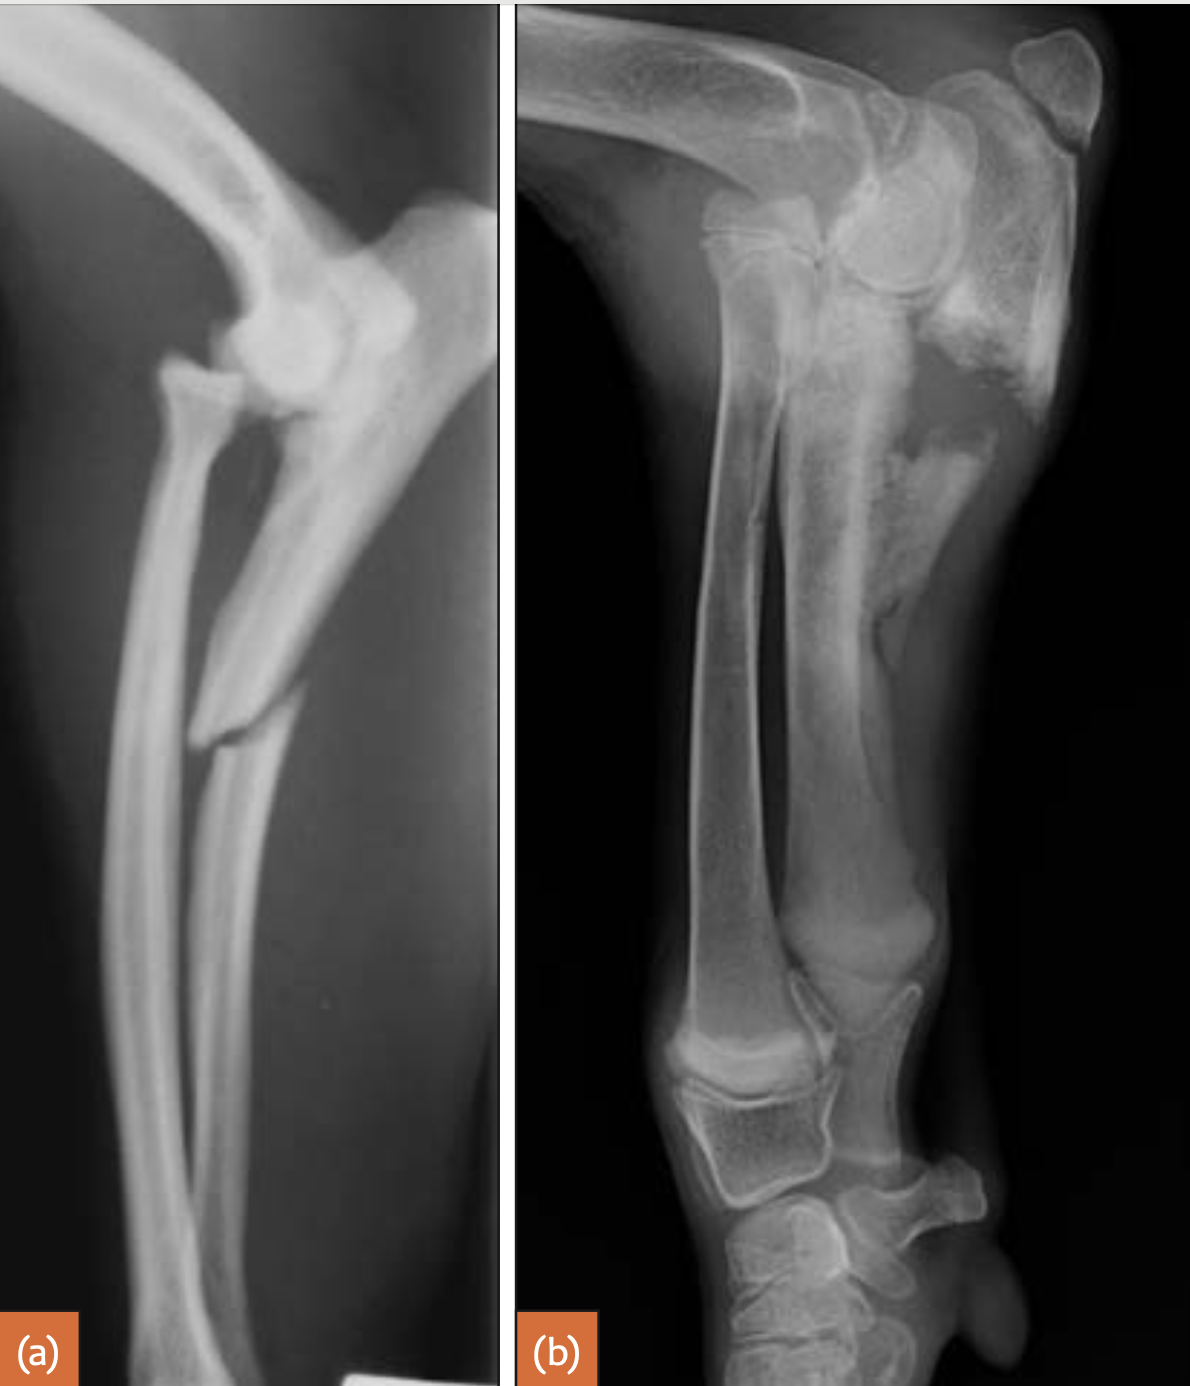

5m JRT

Congenital proximal radial luxation or subluxation usually occurs in larger breeds such as Shetland Sheepdogs and Bulldogs. Clinically, there may be only mild deformity or lameness. The radius usually luxates caudolaterally. The radial head is often underdeveloped and rounded.

27

Proximal ulnar luxation is the most common form of primary/congenital elbow luxations and presents with marked limb dysfunction. It is mainly seen in small breeds such as the Yorkshire Terrier and Boston Terrier, as well as the Cocker Spaniel, English Bulldog and Staffordshire Bull Terrier. The ulna usually luxates laterally. The anconeal process may be underdeveloped and the ulna rotated 90 degrees, resulting in a lateral projection of the ulna on a CrCd radiograph